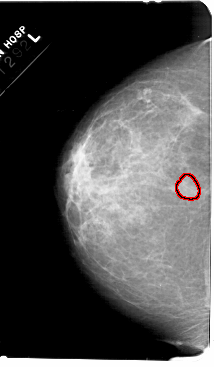

A_1607_1.LEFT_MLO

LEFT_MLO LINES 5491 PIXELS_PER_LINE 3406 BITS_PER_PIXEL 12 RESOLUTION 43.5 OVERLAY

FILE: A_1607_1.LEFT_MLO.OVERLAY

TOTAL_ABNORMALITIES 1

ABNORMALITY 1

LESION_TYPE MASS SHAPE OVAL MARGINS OBSCURED

ASSESSMENT 3

SUBTLETY 2

PATHOLOGY BENIGN

TOTAL_OUTLINES 1

BOUNDARY